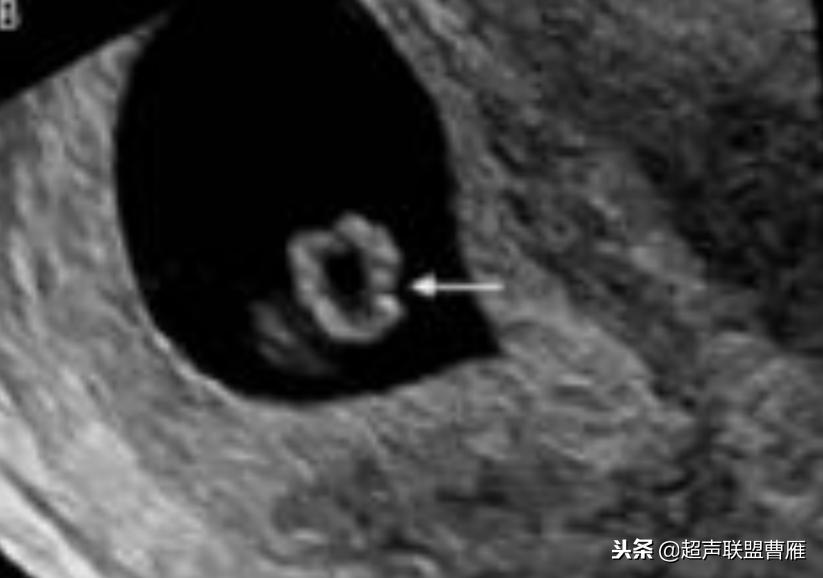

· 正常情况下,卵黄囊中央表现为无回声,周边为厚薄均一、边界清晰的环形高回声。

正常早孕卵黄囊声像图

早孕 胚芽 卵黄囊

5周+ 、6周+ 声像图

孕7周左右(胚芽11mm 卵黄囊)

胎芽 卵黄囊 心管搏动信号

宫内早孕 (7周左右)

正常宫内胚胎组织、卵黄囊